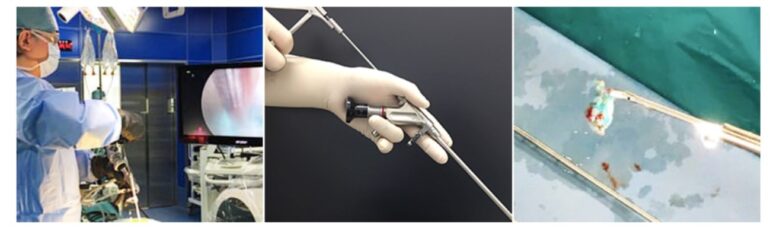

当院では専用の内視鏡を使用して、ヘルニアの摘出や椎弓切除を行う全内視鏡下脊椎手術を導入しています。従来法と比べて体への負担がとても少ない術式で、手術時間は症例にもよりますが、30分~1時間程度です。手術後の痛みも軽く、個人差はありますが、術後3時間から歩行が可能となり、術後3日ほどで退院ができます。

早期の社会復帰が可能であり、忙しい社会人の方でも安心して手術を受けられます。

内視鏡手術が困難な場合もございますので詳しくは外来でご相談ください。

手術時間は30分~1時間程度と短いため、内視鏡の手術の場合は次の日に退院が可能です。切開手術の場合でも術後5日ほどで退院ができます。